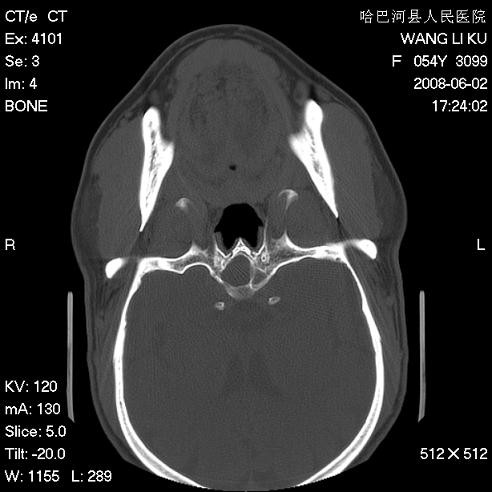

标题: CT13803:反复性鼻塞、流涕一年余 [打印本页]

标题: CT13803:反复性鼻塞、流涕一年余

副鼻窦炎,右上额窦积脓。左眼肌锥内见致密影,视神經受压

1.全组副鼻窦炎2.双侧上颌窦积液

1)全副鼻窦炎(左侧上颌窦黏膜下囊肿或息肉)。2)左眼眶肌锥内不规则小结节状软组织密度影;考虑为小血管瘤可能。建议行ct增强扫描检查。

全组副鼻窦炎,左侧肌锥内不规则形软组织肿块影,与眼外肌密度相当,左侧视神经受压,肿块与视神经及眼外肌分界清晰,眼外肌无增粗,眶壁无破坏,球后脂肪间隙不模糊,考虑良性改变,小血管瘤或神经源性肿瘤可能,建议增强扫描。

谢谢,增强扫描做了,眶内病灶与海绵窦同步明显强化,血管瘤